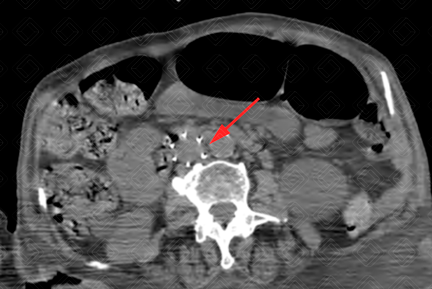

Texto alternativo para a imagem Créditos: Dra. Elazir Mota - Rio de Janeiro/RJ

Descrição das imagens: Tomografia computadorizada do abdome. Filtro metálico na veia cava inferior, de localização infrarrenal (setas vermelhas).